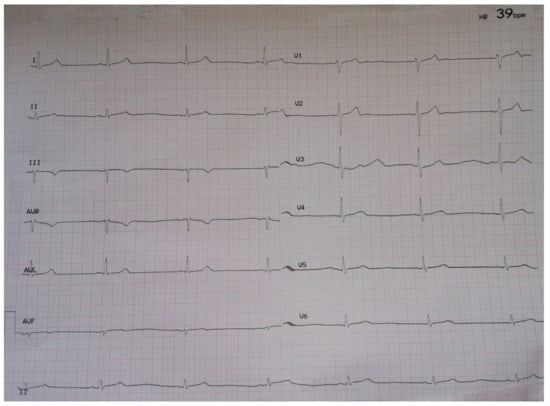

Sinus Bradycardia Associated with Remdesivir Treatment in COVID-19: A Case Report and Literature Review

2. Case Presentation